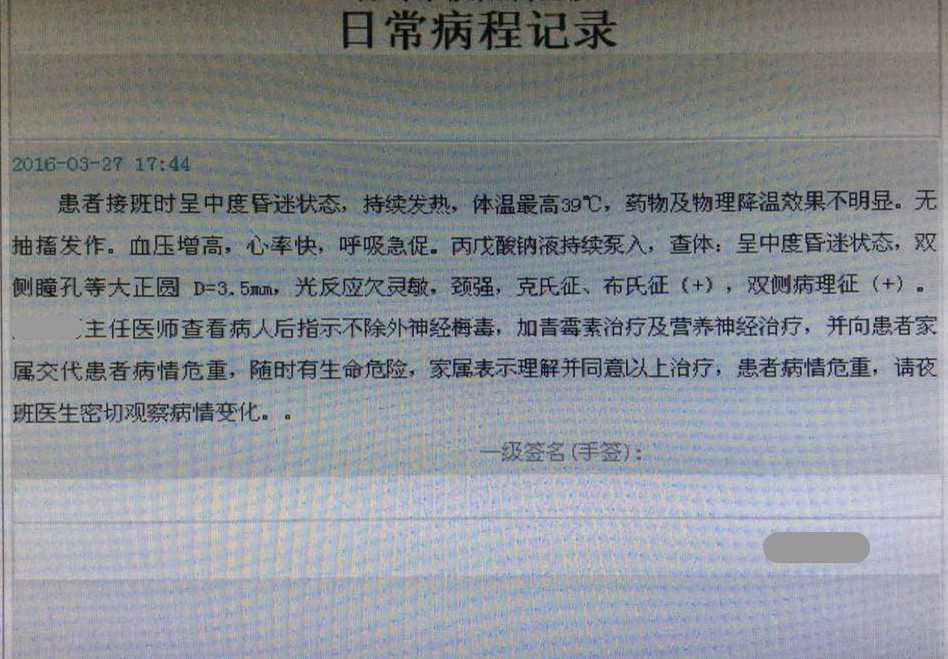

M老师好!我是CX医院神经科Z,98—99年在BX医院神经科进修,当时就是您带我,不知道老师还记得我不?这个患者已经不行了,家属放弃了,抗生素给的头孢曲松+青霉素行吗?同时抗痨,神经梅毒看的少,是不是起病不会这么急?有不洁性生活史

Z大夫好。想起你了,真的很巧。这个患者起病太凶险,还像个细菌感染,或结核。梅毒都是慢性的。如果患者家属不放弃,抗生素治疗还要加强。急性脑膜炎的治疗,急性期都是抗结核,抗生素,抗病毒,都用,3天~7天内调整。有时感染原因确定困难。